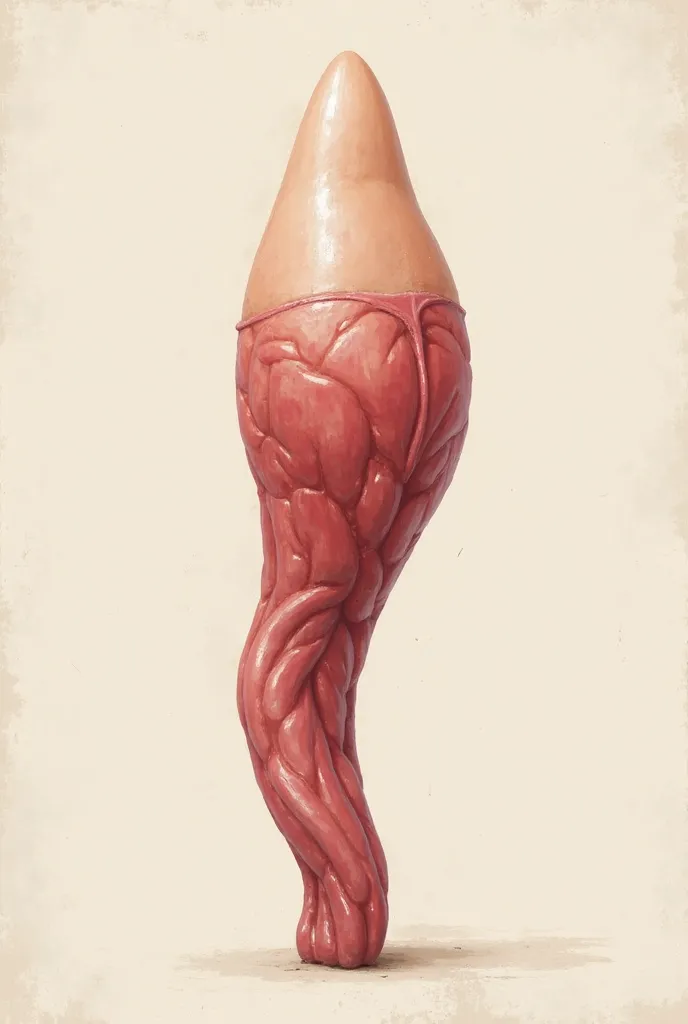

A diagram of the anatomy of the human body